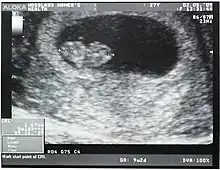

An ultrasound showing an embryo measured to have a crown-rump length of 1.67 cm and estimated to have a gestational age of 8 weeks and 1 day

Crown-rump length (CRL) is the measurement of the length of human embryos and fetuses from the top of the head (crown) to the bottom of the buttocks (rump). It is typically determined from ultrasound imagery and can be used to estimate gestational age.

The embryo and fetus float in the amniotic fluid inside the uterus of the mother usually in a curved posture resembling the letter C. The measurement can actually vary slightly if the fetus is temporarily stretching (straightening) its body. The measurement needs to be in the natural state with an unstretched body which is actually C shaped. The measurement of CRL is useful in determining the gestational age (menstrual age starting from the first day of the last menstrual period) and thus the expected date of delivery (EDD). Different human fetuses grow at different rates and thus the gestational age is an approximation. Recent evidence has indicated that CRL growth (and thus the approximation of gestational age) may be influenced by maternal factors such as age, smoking, and folic acid intake. Early in pregnancy gestational age 8 weeks, it is accurate within about +/- 5 days but later in pregnancy due to different growth rates, the accuracy is less. In that situation, other parameters can be used in addition to CRL. The length of the umbilical cord is approximately equal to the CRL throughout pregnancy.